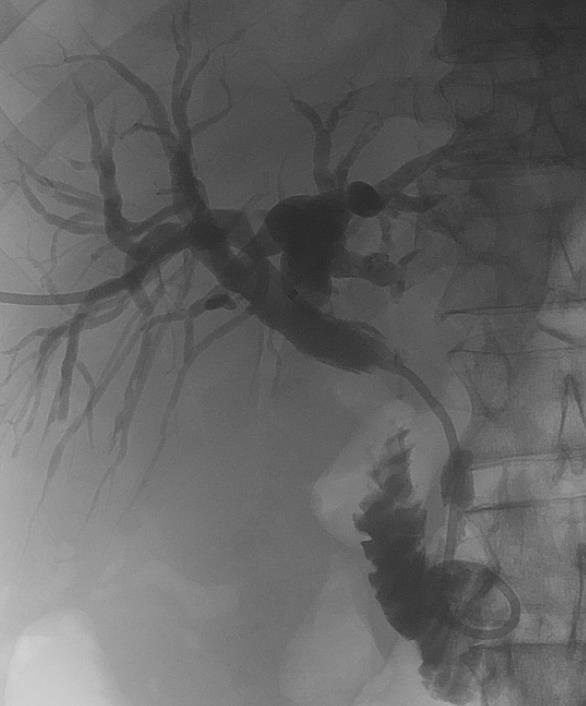

After percutaneous access of the intrahepatic biliary duct was achieved, a long 10Fr sheath was positioned in the common bile duct over an 0.035” guidewire with a second 0.018” guidewire positioned to gain access into the plastic stent.